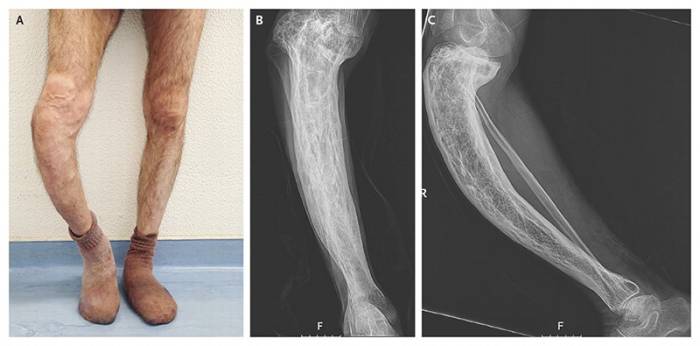

Патология затрагивает костные структуры, нарушая процесс рециркуляции веществ, в результате чего старая костная ткань постепенно заменяется новой. Эти патологические изменения могут вызвать серьезные проблемы, такие как деформация и хрупкость костей. Чаще всего болезнь затрагивает таз, позвоночник и нижние конечности (фото).

- Поражение ног вызывает общую слабость и деформацию костей. Это увеличивает нагрузку на соседние суставы, что может привести к развитию остеоартрита. Чаще всего страдают бедра и колени.

Диагностика болезни Педжета осуществляется с помощью рентгенографии костей. В некоторых случаях врачи могут рекомендовать проведение биопсии. Тепловизионное исследование помогает выявить участки мягких тканей с повышенной температурой над пораженными костями.